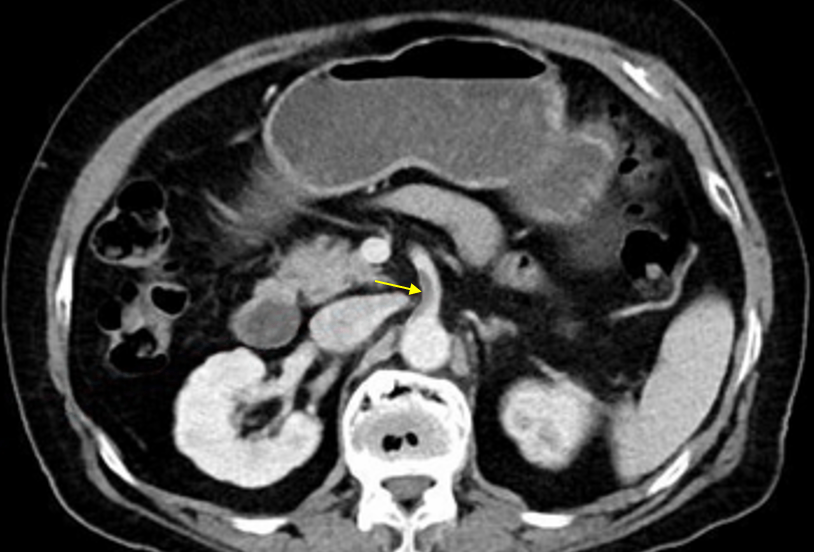

Img | CT: SMA thrombosis |

복부 전체의 갑작스러운 반동압통, AF 병력, CT의 SMA thrombosis로 보아 SMA occlusion을 진단할 수 있다.

• 실제로 CT상 aorta에서 기시하는 SMA의 proximal 부분에 thrombus가 관찰되며, 이로 인해 intestinal ischemia가 발생한 것으로 추정된다. 따라서 SMA occlusion으로 진단할 수 있다.